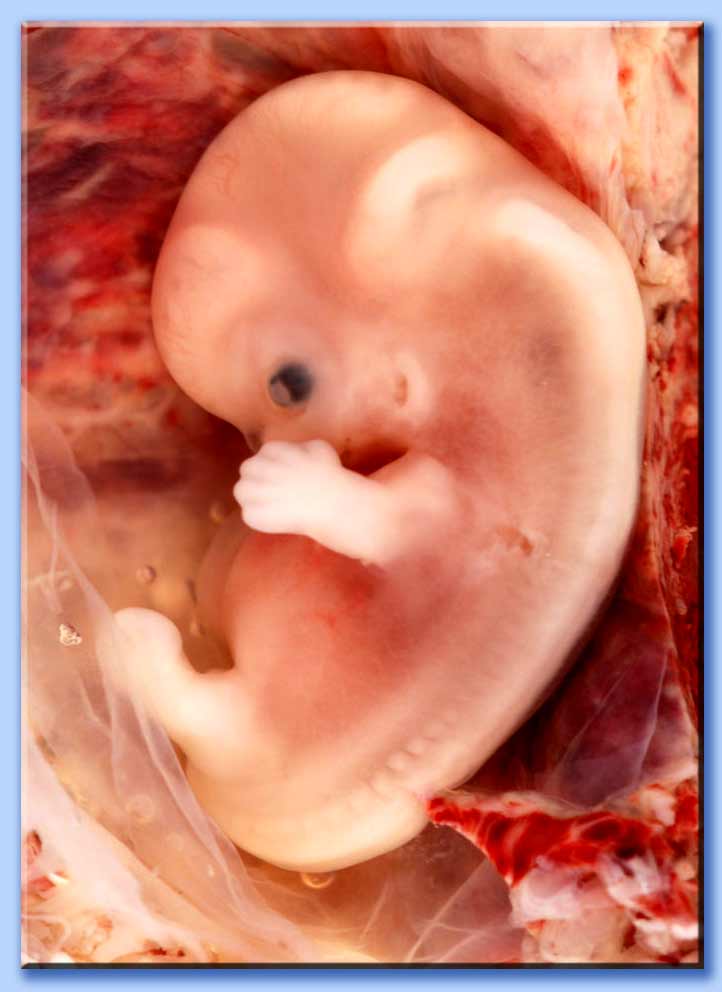

Ecografia Di Un Embrione 8 Settimane Fotografie Stock E Altre Immagini Di Addome Istock

Feto A 8 Settimane Foto

Cm Embrione A 8 Settimane

Feto Dalla Settimana 8 Alla 12 Sito Ufficiale Chicco It

8 Ottava Settimana Di Gravidanza Pancia E Dimensioni Feto